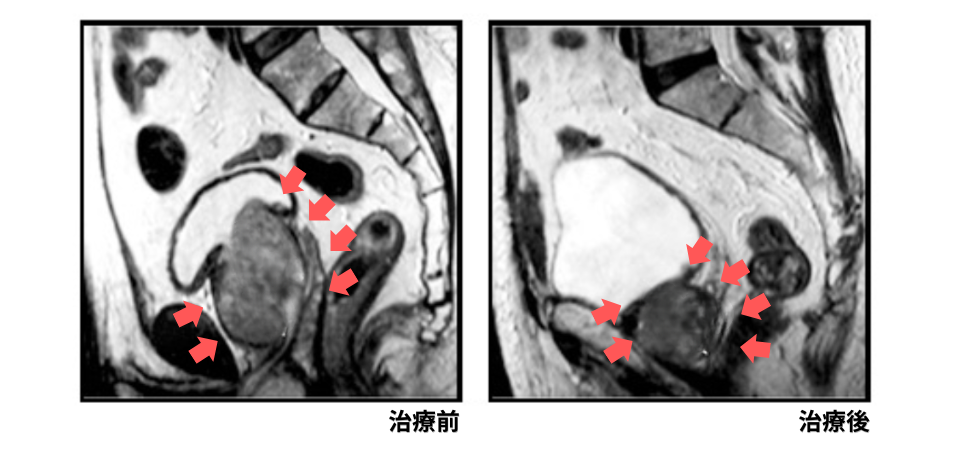

PAEの治療後、最初の2〜3日は一時的に頻尿や排尿痛が出ることがありますが、これは前立腺にしっかりと薬が効き、治療がうまくいっている証拠です。その後、数週間から1ヶ月ほどかけて徐々に前立腺が縮小し、画像検査でも前立腺が明確に小さくなったことが確認できました(下記画像参照)。

前立腺が縮小したことで尿道の圧迫が取れ、一番の悩みだった夜間頻尿も大きく改善。長年悩まされていた睡眠障害から解放され、前立腺を削る手術による性機能低下のリスクも避けて、無事に生活の質(QOL)を取り戻すことができました。